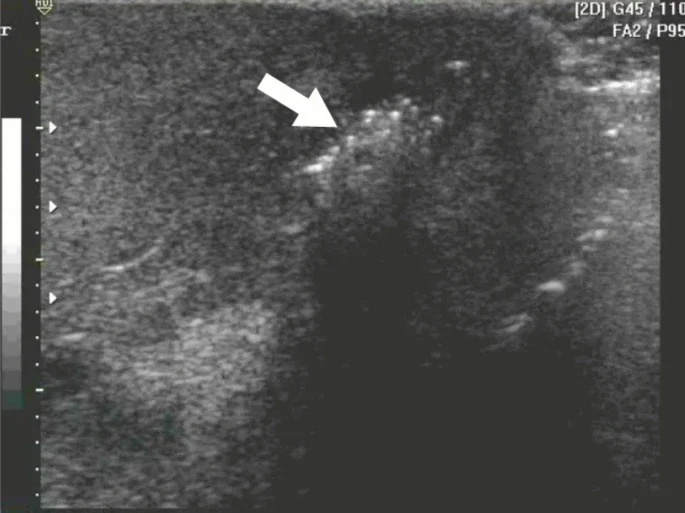

Similar appearing pathology

• The appearance of the hyperechoic punctate lesions may initially raise concern for air.

• Reminder: air appears as hyperechoic punctate lesions on ultrasound with shadowing behind it. Think: bowel gas, necrotizing fascitis

• However, testicular microlithiasis does not exhibit shadowing and as mentioned above, this is often an incidental finding that is not associated with any concerning acute symptoms.

• Here is an example of air in the scrotum, concerning for Fournier’s Gangrene. You would expect clinical symptoms concerning for necrotizing infection such as pain, foul smelling discharge, necrotic tissue, fever.